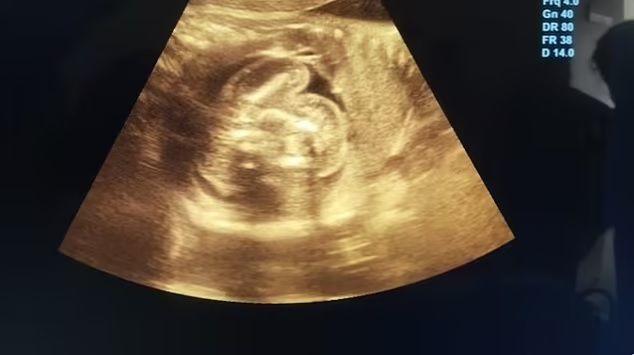

사진=데일리메일 홈페이지

임신 중인 태아의 뱃속에 또 다른 두 명의 태아가 자라고 있는 희귀한 사례가 포착돼 화제다.

19일(현지시각) ‘데일리메일’ 보도에 따르면 인도의 한 32세 임산부의 태아 복부 안에서 두 명의 기형 태아가 추가로 발견됐다. 이 여성은 임신 35주 차에 정기 검진을 받기 위해 지역 병원에 방문했다가 태아의 뱃속에서 이전 검진에서 발견되지 않던 뼈를 포함한 조직을 발견하게 됐다.

추가 검사 결과, 이는 매우 드문 ‘태아 속의 태아(fetus in fetu)’ 현상으로 밝혀졌다. 이 현상은 의학 문헌에 약 200회 정도 기록돼 있으며, 그 중 태아의 뱃속에 둘 이상의 태아가 있던 사례는 몇 건인지 확실하지 않을 정도로 희귀한 사례다.